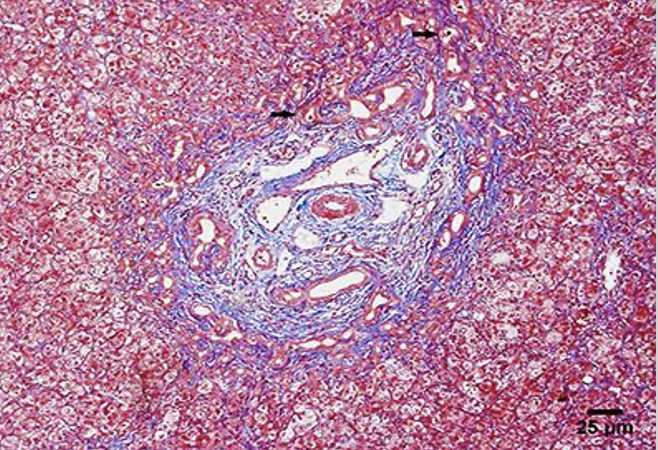

23

Q

trichrome stain of what

A

portal fibrosis

24

fibrosis of ducts